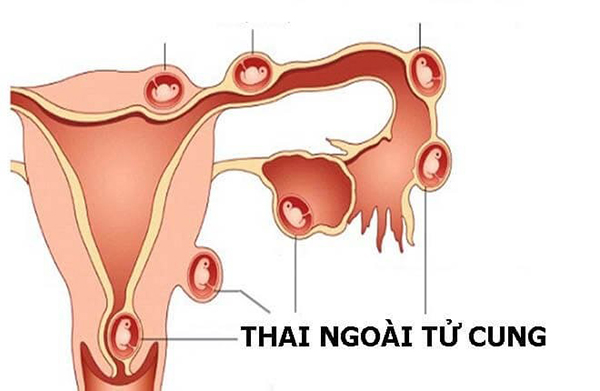

Thông thường, phôi thai phải làm tổ trong buồng tử cung của phụ nữ. Tuy nhiên, trong một số trường hợp cá biệt, thai làm tổ ở bên ngoài buồng tử cung. Vị trí cụ thể với từng trường hợp khác nhau. Có thể là thai làm tổ ở vòi tử cung. Hoặc làm tổ ở ổ bụng, ở cổ tử cung, buồng trứng. Thậm chí có trường hợp thai còn làm tổ ở ngay vết mổ đẻ cũ. Các trường hợp này không hiếm gặp trong thực tế. Do vậy, nhiều người thắc mắc không biết thai ngoài tử cung siêu âm có thấy không.

Bất cứ tình trạng bệnh lý gì cũng có nguyên nhân của nó. Mang thai ngoài tử cung cũng vậy. Nguyên nhân dẫn đến tình trạng này có thể do phụ nữ trước đó từng nạo phá thai nhiều lần. Người mẹ mắc các bệnh truyền nhiễm đường tình dục. Mẹ bầu bị viêm nhiễm âm đạo dẫn đến viêm nhiễm vòi trứng, vùng chậu. Hoặc cũng có trường hợp là do bản thân người mẹ có ống dẫn trứng bị dị tật, hẹp ống dẫn trứng, bị u nang buồng trứng.

Thông thường, khi mẹ bầu bị trễ kinh lâu ngày và có hiện tượng mang thai thì đi khám. Bác sĩ khi siêu âm tử cung không thấy thai làm tổ sẽ chỉ định siêu âm ổ bụng để xem thai làm tổ ở đâu. Nếu không thấy thì sẽ tiến hành siêu âm đầu dò bằng cách dùng một dụng cụ đưa vào cổ tử cung. Đầu dò sẽ cho hình ảnh chính xác và độ nhạy cao. Siêu âm được các bộ phận buồng trứng, vòi tử cung, ống dẫn trứng… Như vậy sẽ dễ dàng tìm thấy và xác định được vị trí làm tổ của phôi thai.